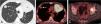

(A) Axial thoracic contrast-enhanced CT image (lung window) shows a large left upper lobe mass (asterisk) and a smaller right upper lobe nodule (arrow). (B) Axial fused PET/CT image demonstrates intense FDG uptake by the left upper lobe mass (asterisk) but mild FDG avidity by the right upper lobe nodule (arrow), suggesting two synchronous primary lung tumors. (C) Axial fused PET/TC image shows an FDG-avid bone lesion involving the left acetabulum (arrow).

A 67-year-old patient with hemoptysis was found to have 2 lung lesions on CT: a larger pulmonary mass in the left upper lobe and a smaller lung nodule in the right upper lobe (Fig. 1A). An 18F-fluorodeoxyglucose (FDG) positron emission tomography/CT (PET/CT) ruled out mediastinal involvement and showed that the FDG-avidity of the bilateral lung lesions was markedly different (maximum standardized uptake value [SUVmax] of left upper lobe mass: 9.4; SUVmax of right upper lobe nodule: 2.9), suggesting the possibility that the 2 lung lesions corresponded to synchronous primary lung tumor (Fig. 1B). PET/CT also confirmed a single bone metastasis in the left acetabular roof (Fig. 1C) showing intense FDG uptake (SUVmax; 10.2). The tumor board discussed these findings and finally agreed that the patient most likely had 2 primary lung tumors: one in the left upper lobe (cT4N0M1b with a single bone metastasis) and one in the right upper lobe (cT1bN0M0). The multidisciplinary decision was made to percutaneously biopsy the two pulmonary lesions. Since the patient was taking antiplatelet therapy, the interventional thoracic radiologist proposed performing a “double” CT-guided core needle biopsy in one single session with the intention not to discontinue twice his antiplatelet medication, thus avoiding risks related to the suspension of this drug. The “double” CT-guided biopsy procedure was performed under local anesthesia sequentially during the same interventional session: first, the lung lesion with the lowest anticipated risk of pneumothorax was biopsied (the left upper lobe mass) and, afterwards (once pneumothorax was ruled out following the first lung biopsy), the contralateral lung lesion (the right upper lobe nodule) was biopsied (Fig. 2A, B). Both pulmonary lesions were biopsied using an 18 G cutting needle (different coaxial biopsy system for each lesion) under CT guidance, and 3 tissue samples were obtained from the left upper lobe lung mass whereas 2 tissue samples were obtained from the right upper lobe lung nodule. The “double” lung biopsy was uneventful (no pneumothorax or lung hemorrhage occurred) and the patient was discharged 6 h later, once a chest X-ray performed 3 h after the biopsy ruled out a delayed pneumothorax. The pathological diagnosis initially confirmed that these 2 lung lesions represented 2 malignant primary lung tumors (two squamous cell carcinomas with different immunohistochemical profile). Comprehensive next-generation sequencing (NGS) was not performed on the specimens obtained from both lung lesions. The patient started treatment with a combination of chemotherapy and immunotherapy; in addition, it was decided to treat with stereotactic radiotherapy both the single bone metastasis and the right upper lobe lung nodule.